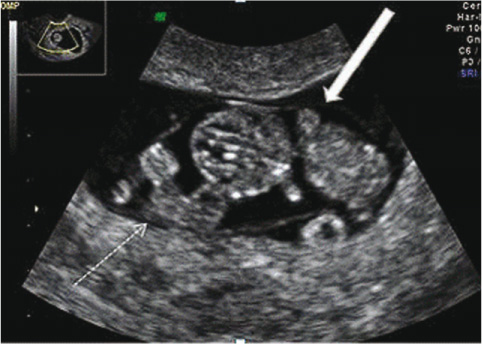

A 27-year-old, gravida 2, para 1, first presented at the 8th week of a spontaneously conceived pregnancy. Her obstetric and medical history showed no complications. Detailed transvaginal ultrasound (US) at that time showed a fetus with normal growth. However, in the same gestational sac, a second poorly delineated mass with a single slowly beating heart (89/min) was seen (Figure 1). Differential diagnosis included a monochorionic monoamniotic (MCMA) TRAP sequence, conjoined twin, or dysmorphic fetus.

Detailed transvaginal US at 8 weeks of gestational age showed a fetus with normal growth and a second poorly delineated mass with a single slowly beating heart (89/min).

White dashed arrow, abnormal mass; white arrow: normal fetus.